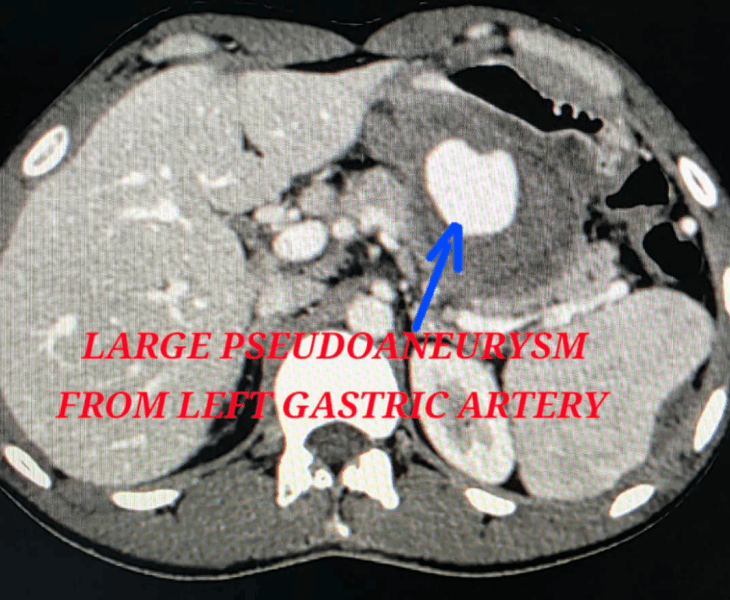

A pseudoaneurysm is a contained arterial bleed where blood escapes the artery through a tear and forms a sac outside the vessel wall. Unlike a true aneurysm, the sac is not made of normal artery wall, so it can rupture and cause severe internal bleeding.

Pseudoaneurysms can occur after trauma, surgery, procedures, pancreatitis or infection. Because they can rupture unpredictably, early diagnosis and prompt embolization is often the safest way to control bleeding.

We use CT angiography and catheter angiography to identify the bleeding vessel precisely and then perform targeted embolization to seal it while preserving as much normal organ blood supply as possible.

- Catheter angiography: contrast is injected to locate the pseudoaneurysm and bleeding source.